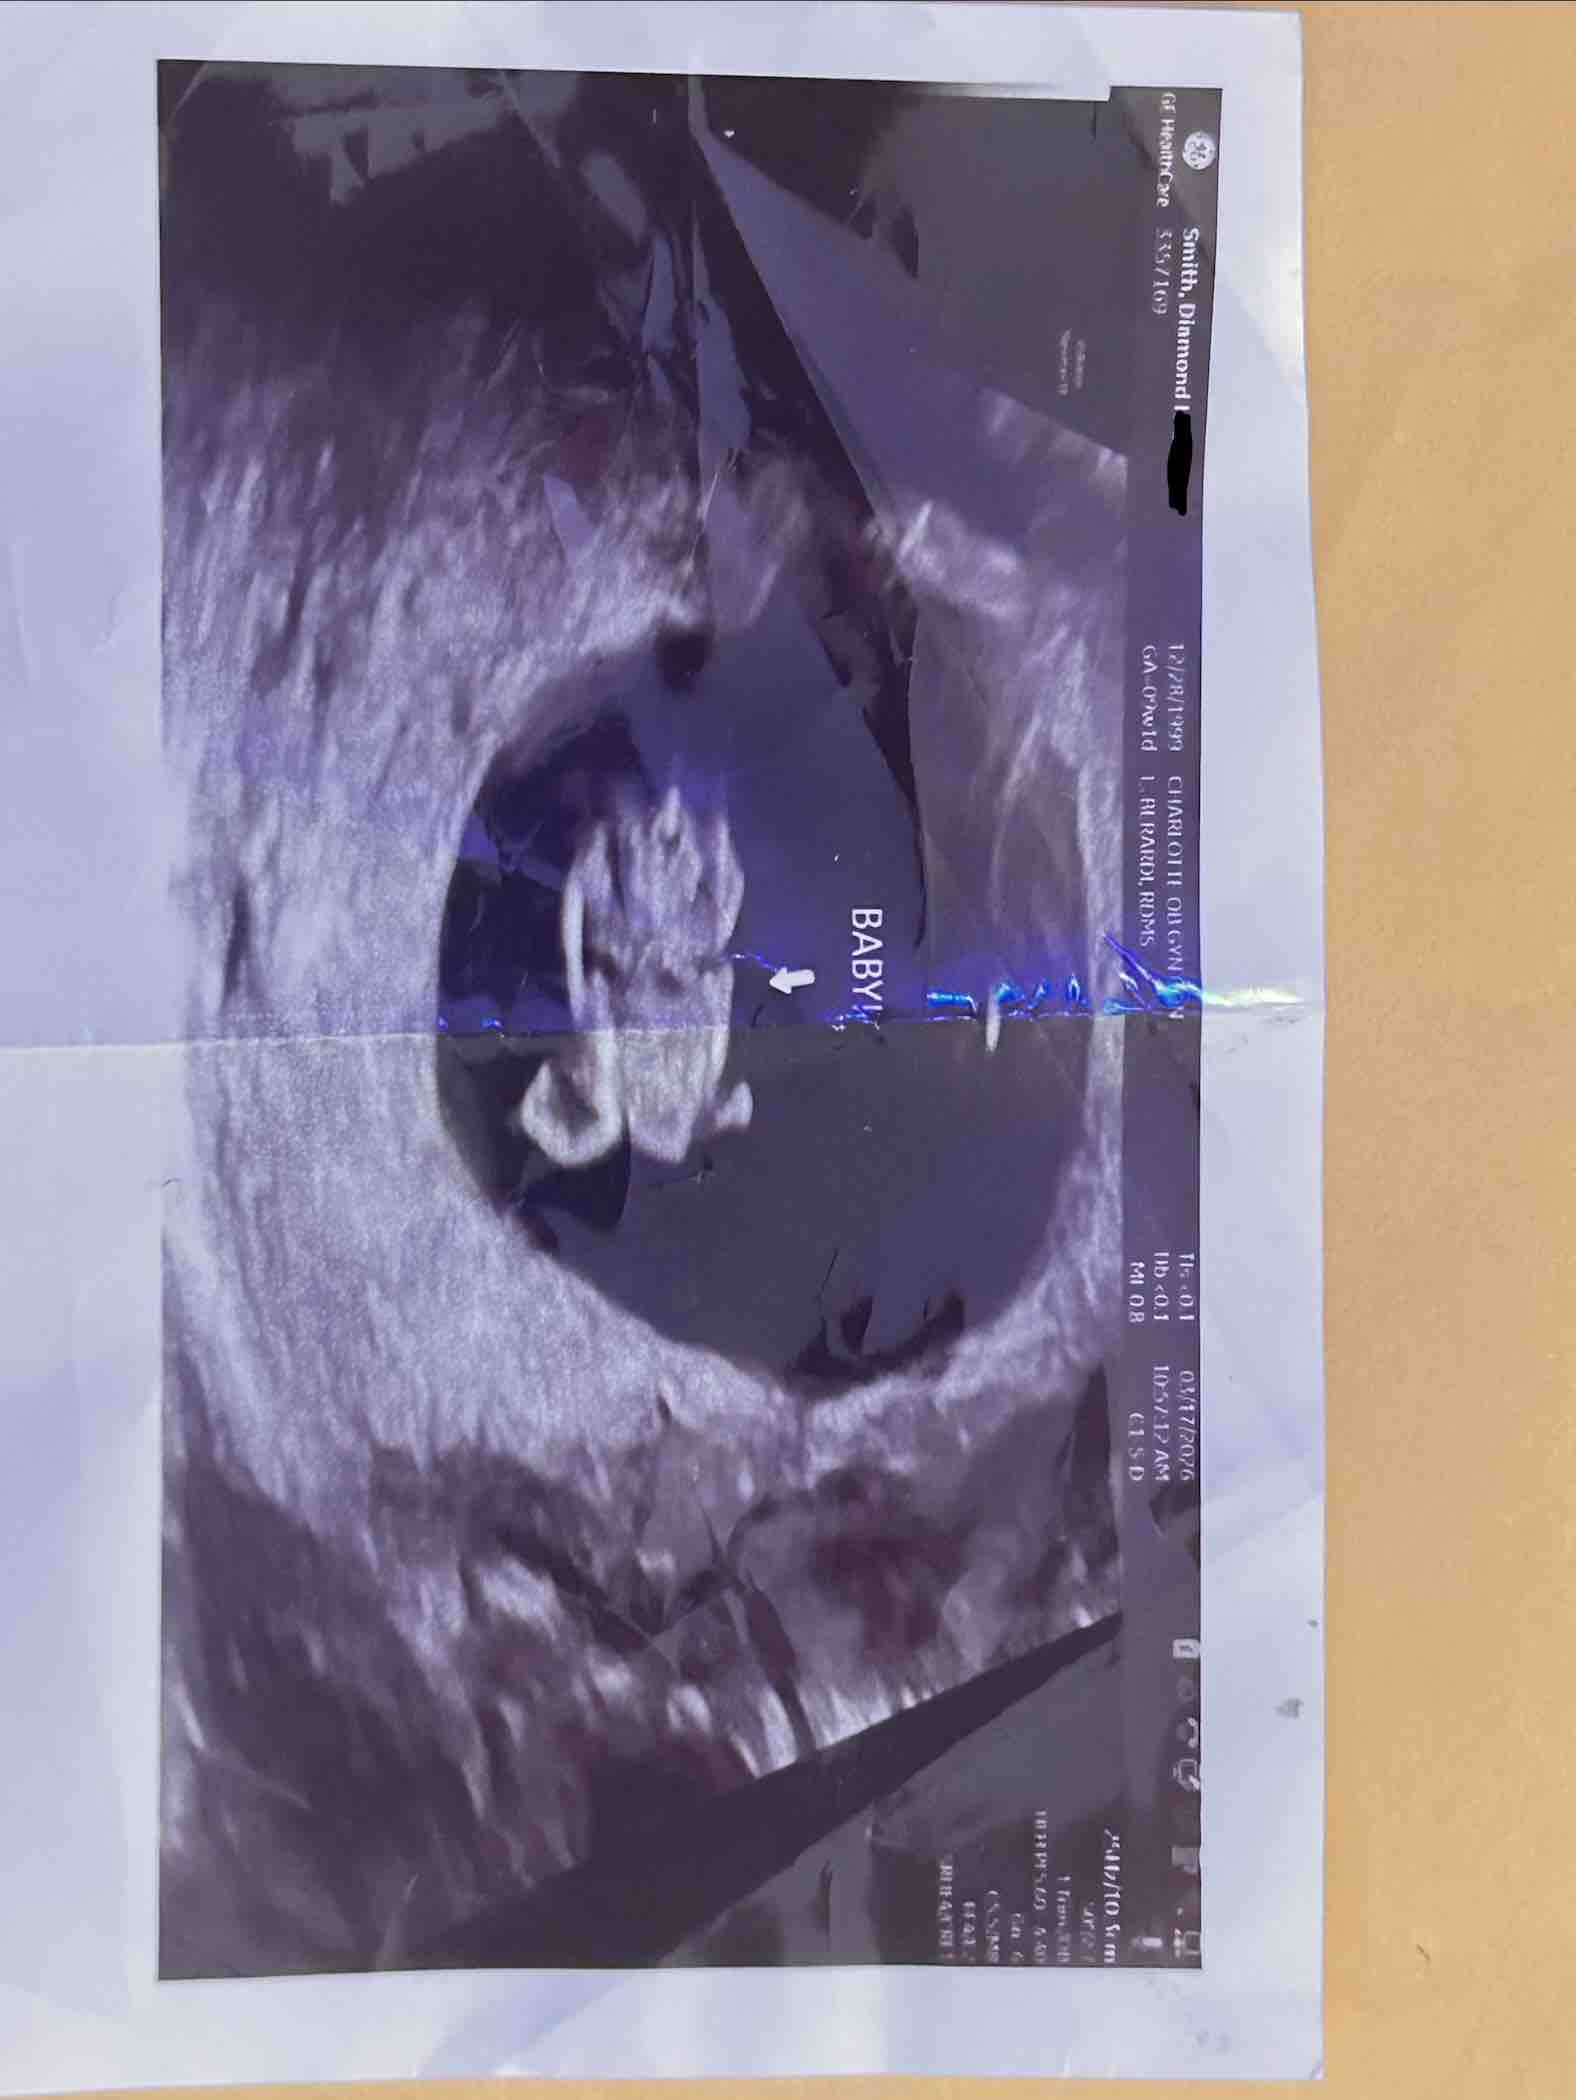

My name is Diamond. I am 26 years old and I am currently about 10 weeks pregnant as of March 23, 2026. I stay with my mom at the moment and things arent the best between us because she just recently admitted to using my credit growing up so im not able to get an apartment nor approved for a car without a cosigner cause she ruined my credit history. I called all the credit bureaus to try to unfreeze my accounts or see what I can do and seems like it’s gonna be a very long process and my due date is in October on the 19th. Not asking people to donate much, but it would be highly appreciated. If I could raise some money to get a used vehicle just for the time being so I can get him back-and-forth to work and do what I have to do to pay off what I can and be able to get a place before October or somewhere around that time. Anything would be highly appreciated. I was gonna look at some used cars on Facebook market or ask around. The lowest down payment in my area is $1200 for a decent used car and that’s honestly all that I need. The father of my child wanted to work things out then all of a sudden decided to switch up on me because he has a lot going on personally with his self which I know doesn’t sound fair, but I just want to avoid confrontation at all cause so I don’t stress.